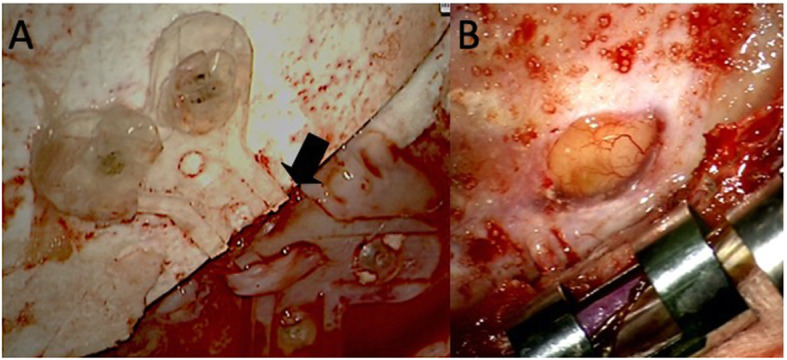

The previous skin incision was made, and the skin flap was flipped. Though we found no fracture of the artificial bone flap, two bioresorbable plates we used previously were both fractured in the middle [Fig. 3a]. After taking off the bone flap, there was a dural tear at the point of the bone edge, and the cerebrospinal fluid was leaking. [Fig. 3b]. We repaired the injured dura with polyglycolic acid (Dura wave®) with fibrin glue. We fixed the bone flap previously used again by a titanium plate. After the repairment, the bulging area vanished, and he was discharged without any adverse effects. We have followed him for 3 years, no troubles have been seen of his skull.

Fig. 3.

Intraoperative photos. a Bioresorbable plates were fractured in the middle (black arrow). b The dural tear at the edge of the bone flap and the cerebrospinal fluid was leaking at this point